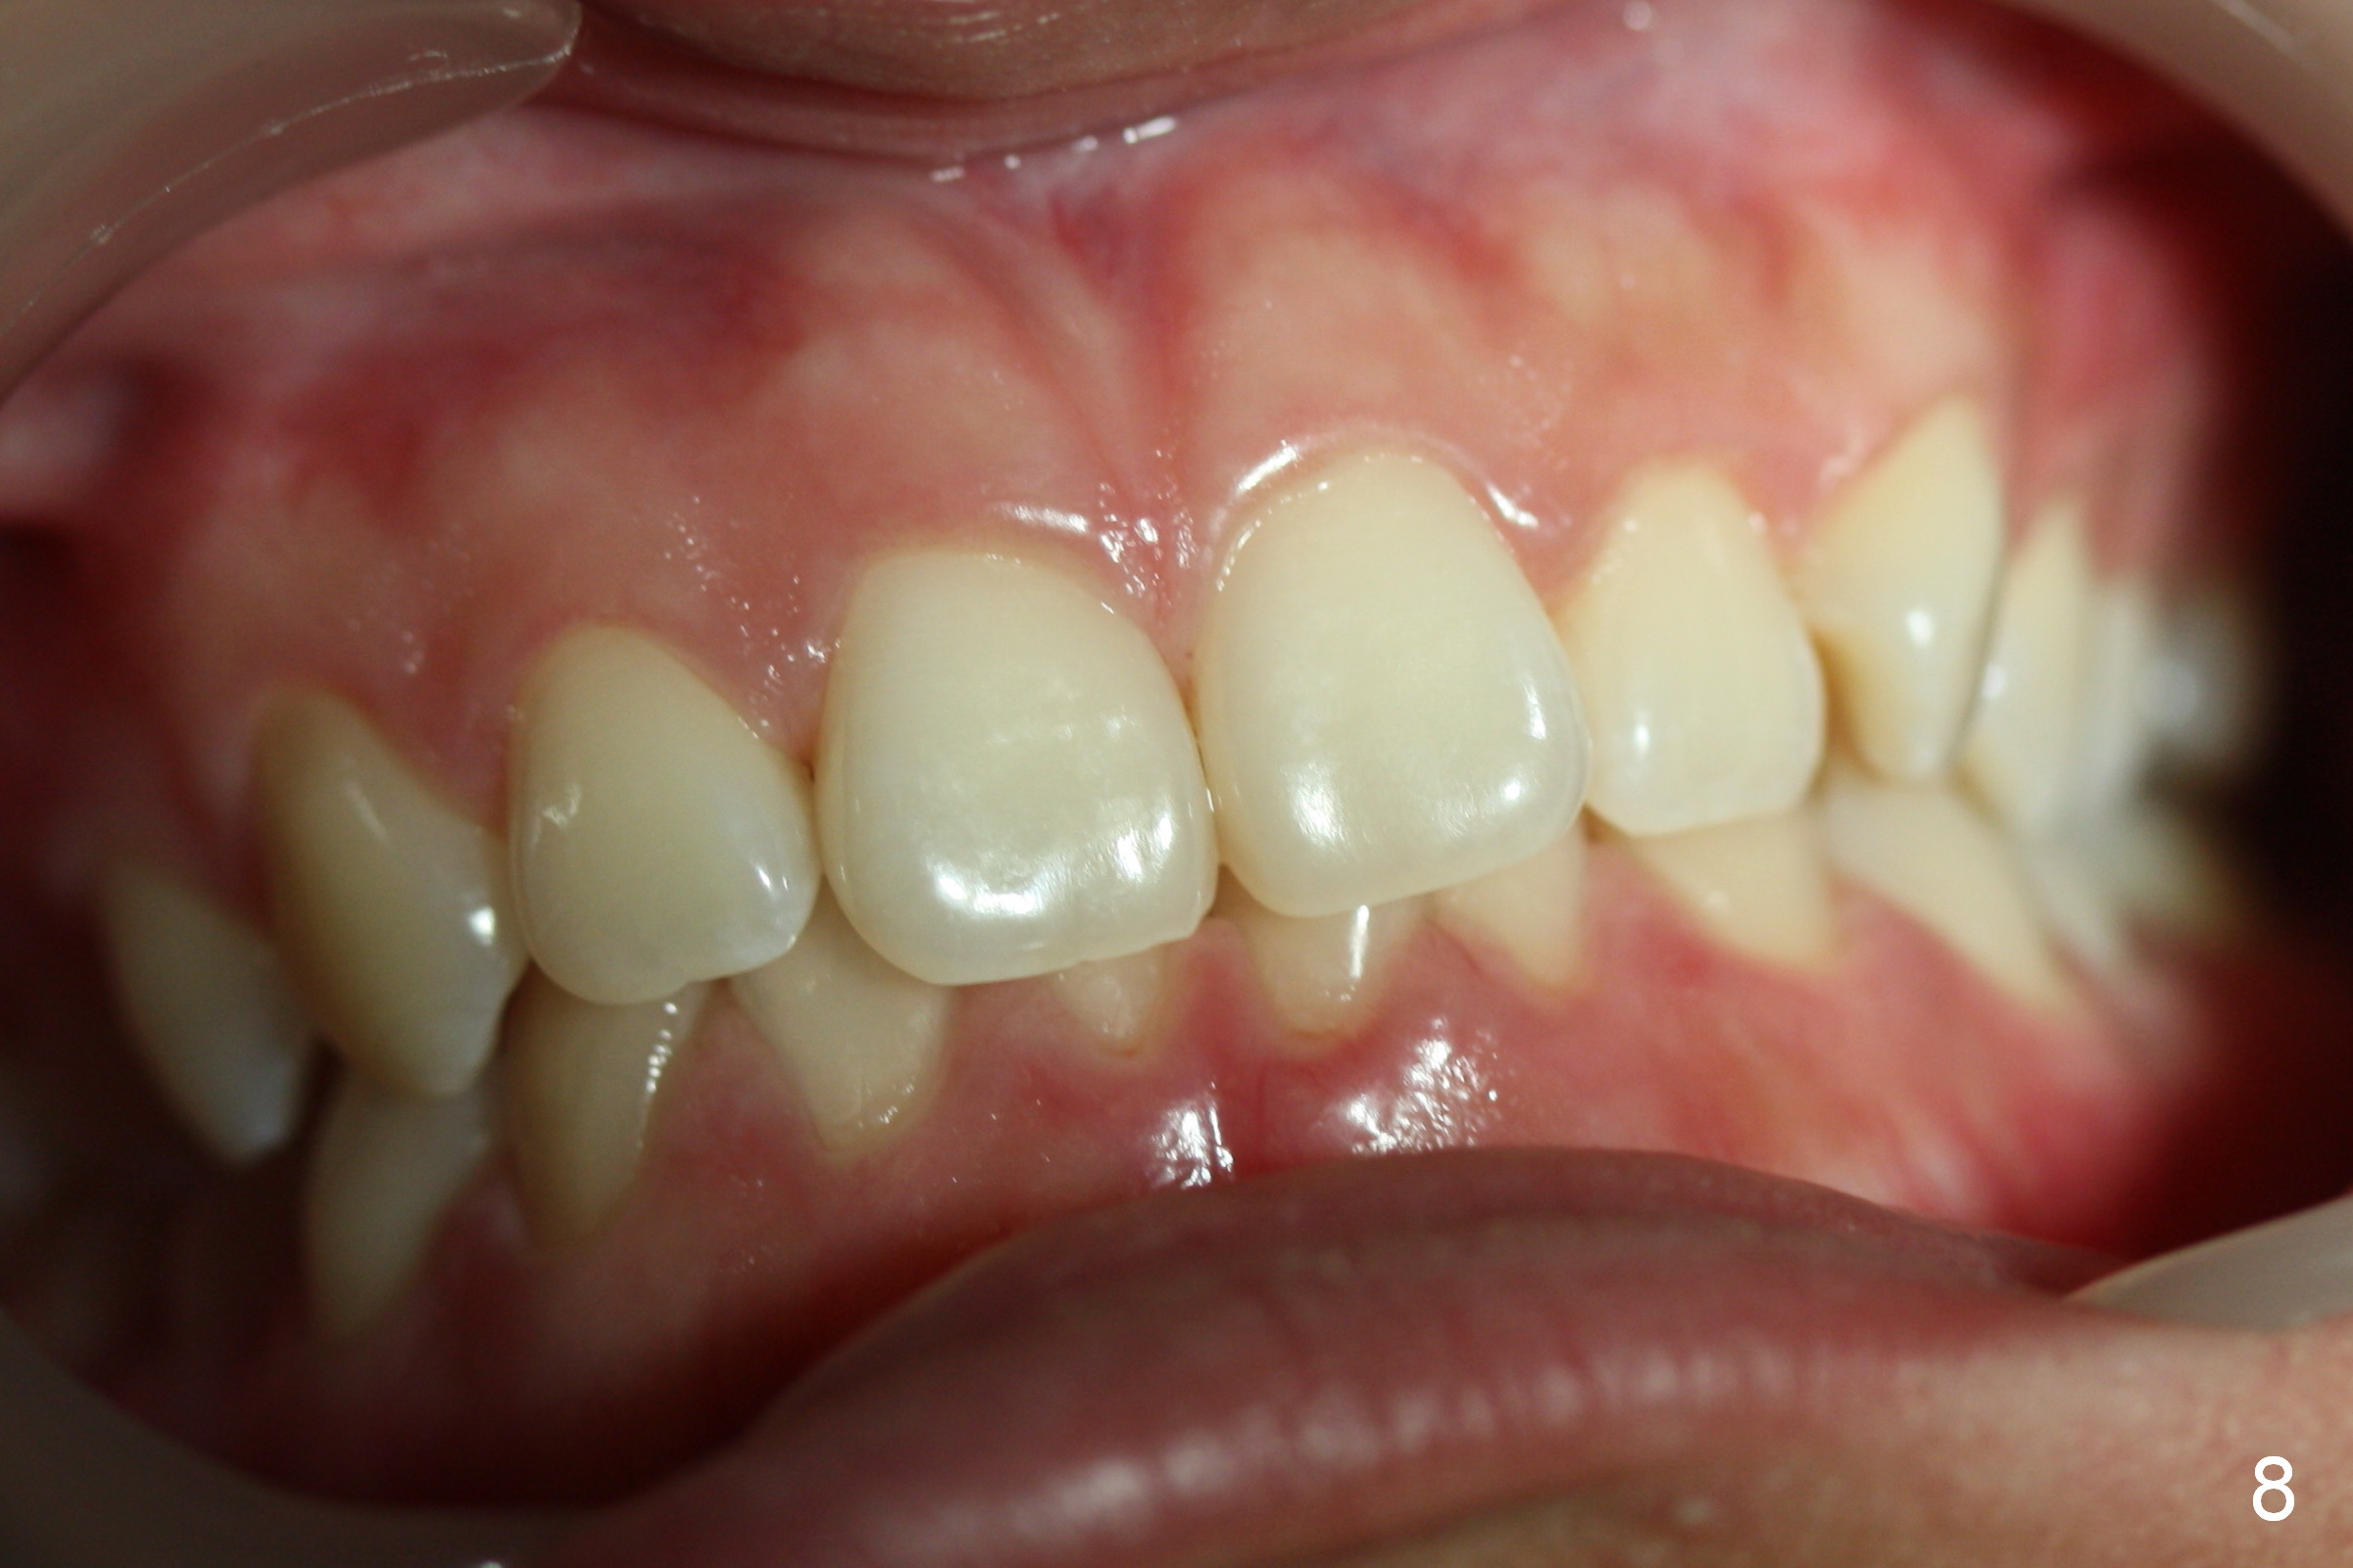

To take the anterior view of the occlusion, let the patient turn the head slightly toward you. The camera frame should be parallel to the imaginary occlusal line. When the photo is not straight (Fig.8), it appears that we are unable to set the teeth straight, either.

Jessica is a 15-year-old Chinese. She cares about her upper central incisors and the upper left canine (rotation). Place rotation wedges as early as possible and overcorrect the rotation.